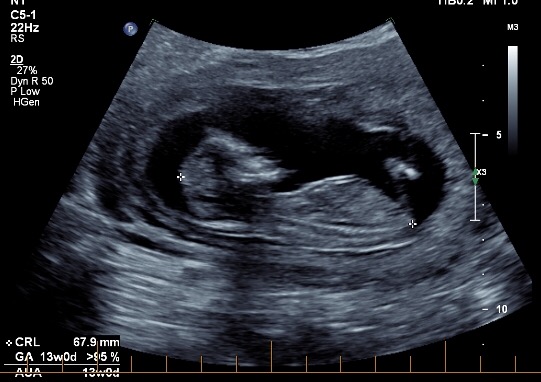

Hi all! I'd love some opinions here, I'm not even sure if there's a nub to see in any of these pictures. These were taken at exactly 13 weeks. I'm now 19 weeks and still have 1 week and 6 days until my anatomy scan (not that I'm counting or anything!) I have three boys and this is my last baby, so I'd love a little girl! Thanks in advance if anyone can help!

Attachment 35248